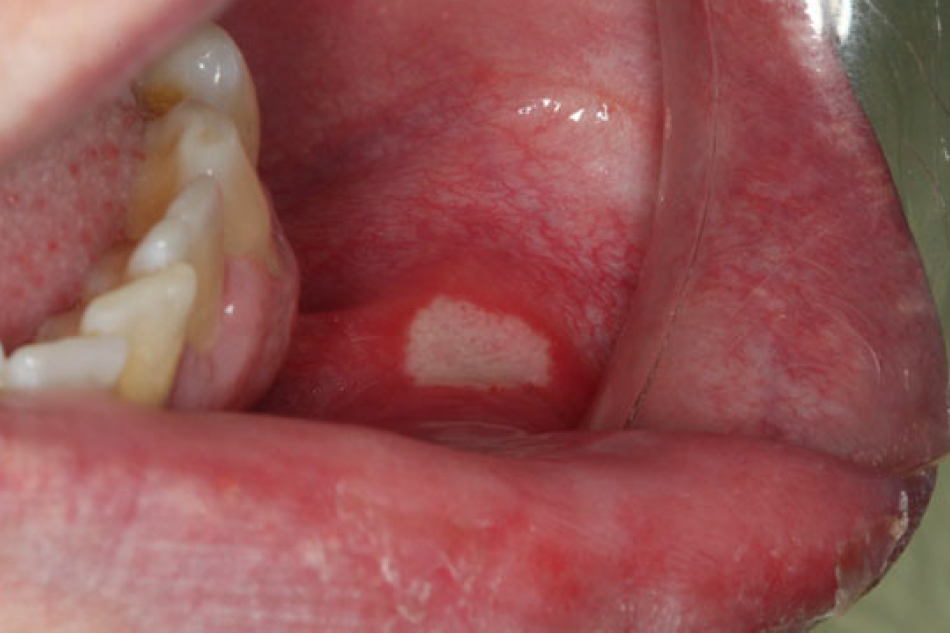

Oral Ulcers. Oral ulcers of several types are seen in association with HIV infection. The most common variety is a severe form of the recurrent aphthous ulceration, which is seen the general population. Aphthous ulcers (Figure 8), also known as canker sores, are not contagious. Other causes of oral ulcers that have been mentioned include lymphoma, herpes group virus infections, mycobacterial ulcers, and, rarely, fungal ulcers caused by histoplasma and cryptococcus. In addition, NUP and a variant that affects soft tissue, necrotizing stomatitis, must be considered in the differential diagnosis. The appearance of some oral ulcers is consistent with recurrent aphthous ulcers. Others are larger, may not be recurrent, and may fall into the category of necrotizing stomatitis. Recurrent aphthous ulcers may range in size from 1 mm to 5 mm for minor aphthae, to as much as 2 cm for major aphthae. The latter may be very persistent and painful and can interfere with speech and swallowing. A typical aphthous ulcer has a red halo and regular margins and is covered with a grayish pseudomembrane.

Figure 8. Aphthous Ulcer (courtesy of dentalcare.com)

Figure 8